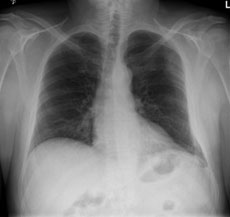

Ein 42-jähriger Freizeitsportler stürzte vor einigen Tagen bei einer Velotour auf die linke Flanke und kommt nun in Ihre Praxis wegen persistierenden thorakalen Schmerzen, v.a. bei tiefer Inspiration.

Sie veranlassen ein Thoraxröntgen, dessen Aufnahmen Sie hier sehen: